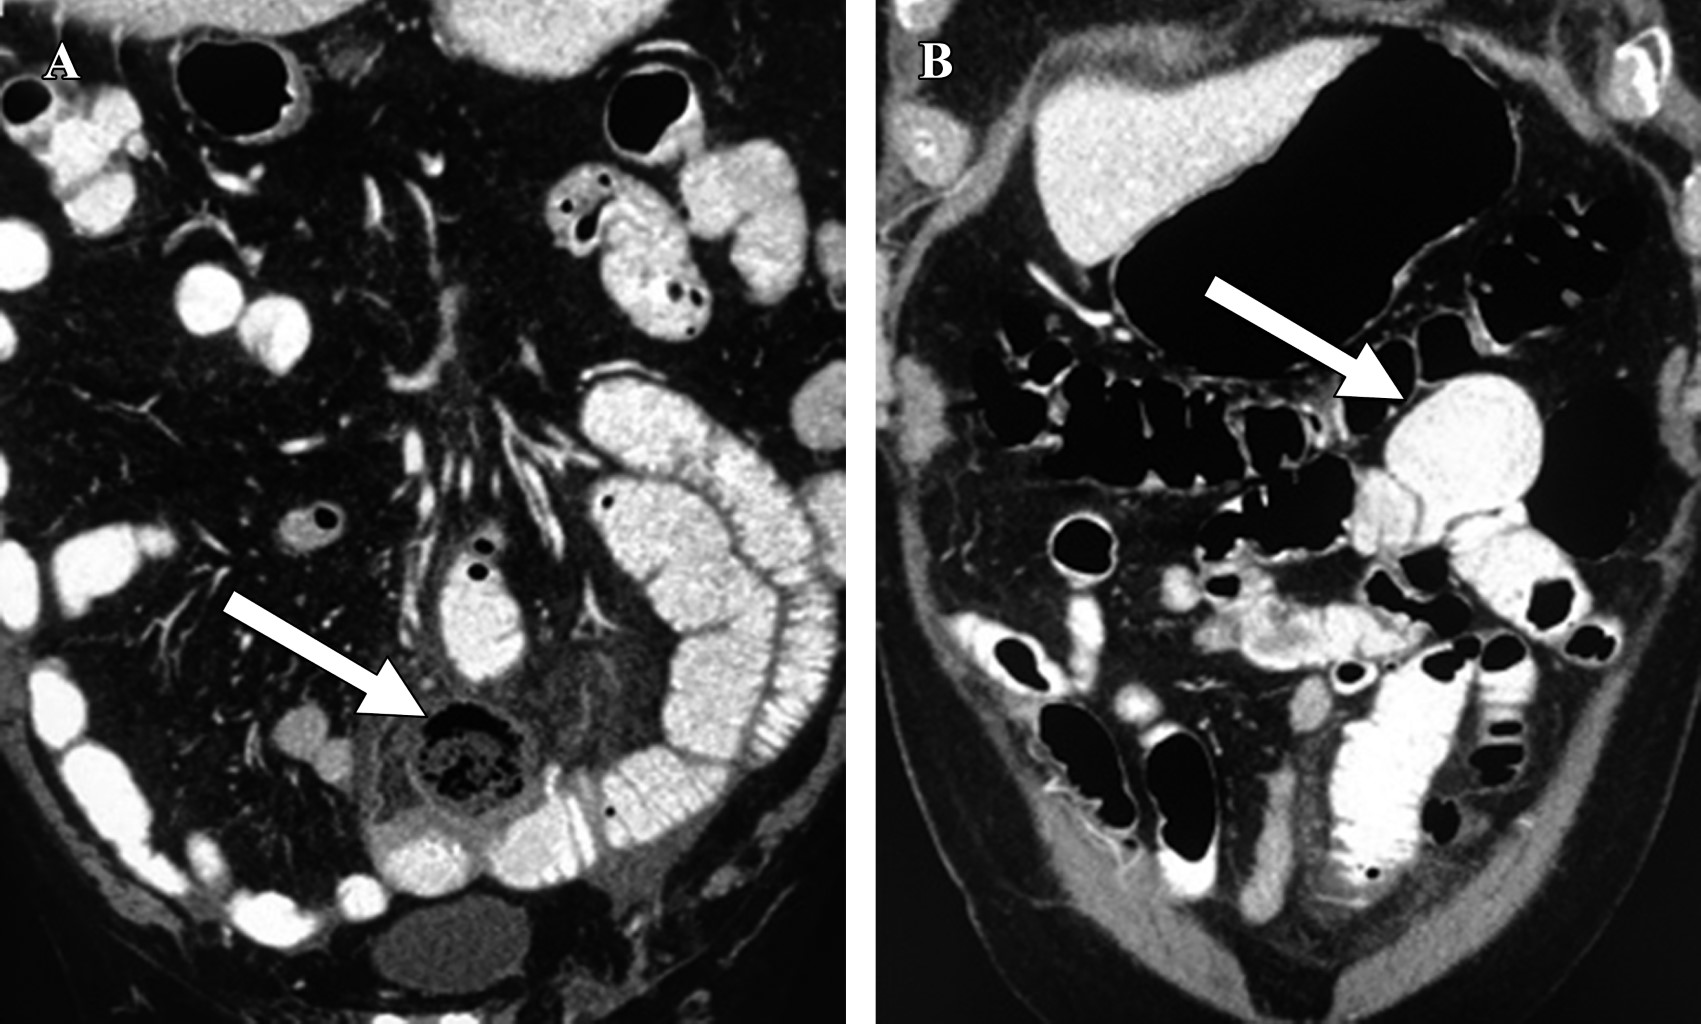

Paciente masculino de 80 años con mal estado general, dolor abdominal de 48 horas de evolución, fiebre, leucocitosis e irritación peritoneal localizada hacia la fosa iliaca izquierda. Antecedentes de dolor abdominal crónico y diarrea atribuidos a síndrome de intestino irritable y diverticulosis sigmoidea. Diagnosticado inicialmente con un cuadro de probable enfermedad diverticular complicada del colon, por lo cual se le solicitó tomografía abdominal contrastada. En dicho estudio, se reportó la presencia de un plastrón inflamatorio asociado a un segmento de intestino delgado en la zona del hipogastrio y líquido libre en la cavidad abdominal. En el segmento intestinal afectado, se observó engrosamiento parietal difuso con estriación del tejido graso del mesenterio y una imagen redondeada de 3.7 cm de diámetro con líquido y aire en su interior dependiente del asa intestinal (Figura 1A). Además, se describieron múltiples imágenes saculares, con contraste en su interior, a nivel de duodeno, íleon, yeyuno (Figura 1B) y colon.

Por otra parte, en los casos de abdomen agudo, donde sí es frecuente la realización de tomografía, es más común encontrarlos. Así como en nuestro caso, aproximadamente 60% de los pacientes puede presentar divertículos múltiples a lo largo del intestino delgado.3 En la tomografía, se describen como imágenes redondeadas, adyacentes al intestino, que contienen medio de contraste, aire y residuo intestinal. Cuando los divertículos son mayores a 3 cm de diámetro, el diagnóstico tomográfico puede ser difícil debido a la similitud con asas intestinales, pero se pueden diferenciar de éstas por la ausencia de válvulas conniventes en su interior.1 En ausencia de tomografía, para la mayoría de las complicaciones, como la perforación o la obstrucción de un divertículo yeyunal, el diagnóstico suele ser un hallazgo transoperatorio.

Figura 1